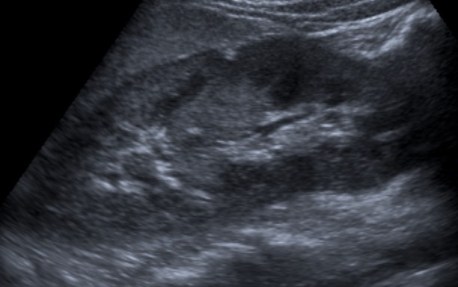

3- Ecografía:

No indicada sistemáticamente.

Tiene varias ventajas, es una prueba con bajo riesgo, barata, disponible, sin radiación y no requiere el uso de material de contraste. Suele ser la primera prueba que se realiza para valorar una pielonefritis. Sin embargo, en adultos es una herramienta que no caracteriza bien la infección renal, por ello, la mayoría de pacientes tienen un resultado negativo, pudiendo demostrar signos en tan solo un 24% de casos y por ello que decimos que infraestima la gravedad de la pielonefritis. Con el uso de material de contraste ecográfico (microburbujas) la S y E de la ecografría es mayor, sin embargo, son necesarios más estudios al respecto.

Cuando se dan hallazgos, lo más frecuente es observar un aumento del tamaño renal, hidronefrosis, litiasis o alteraciones de la vía urinaria. Otros signos que a veces pueden observarse incluyen colecciones, pérdida de definición del seno renal por el edema, focos hipoecoicos por edema o colecciones, focos hiperecoicos de hemorragía, pérdida de diferenciación córtico-medular, áreas hipoperfundidas con baja señal Power Doppler. Las calcificaciones pueden ser difíciles de distinguir del gas. Puede ser limitada para detectar focos de infección perirrenal o abscesos pequeños en infecciones en fases precoces.